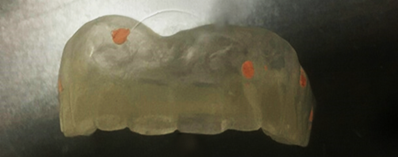

Step 7: Production of the Printed Surgical Guide

In our case, we did indirect digital impressions by using a desktop scanner to convert a Vinyl Polysiloxane Impression Materials impression or a model into a digital impression. Once the maxillary, mandibular, and bite scan files (digital impressions) are ready, export and save them in the highest resolution on the computer in STL format.

Surgical Guide Design

Designing the Surgical Guide is the second step in this workflow. Designing can be done either by using an outside provider, or it may be done in-house by the dentist.

Surgical Guide Fabrication

The appliance can be printed as soon as its design is complete.

Assembly and Sterilization

This stage involves ensuring that the surgical guide is polished, the sleeve is correctly fitted onto the surgical guide, and the surgical guide is completely sterilized.

Figure 17: Guide in progress.

Figure 18: Guide ready to print.

Figure 19: Guide printed with the sleeves and fixations pins placed.